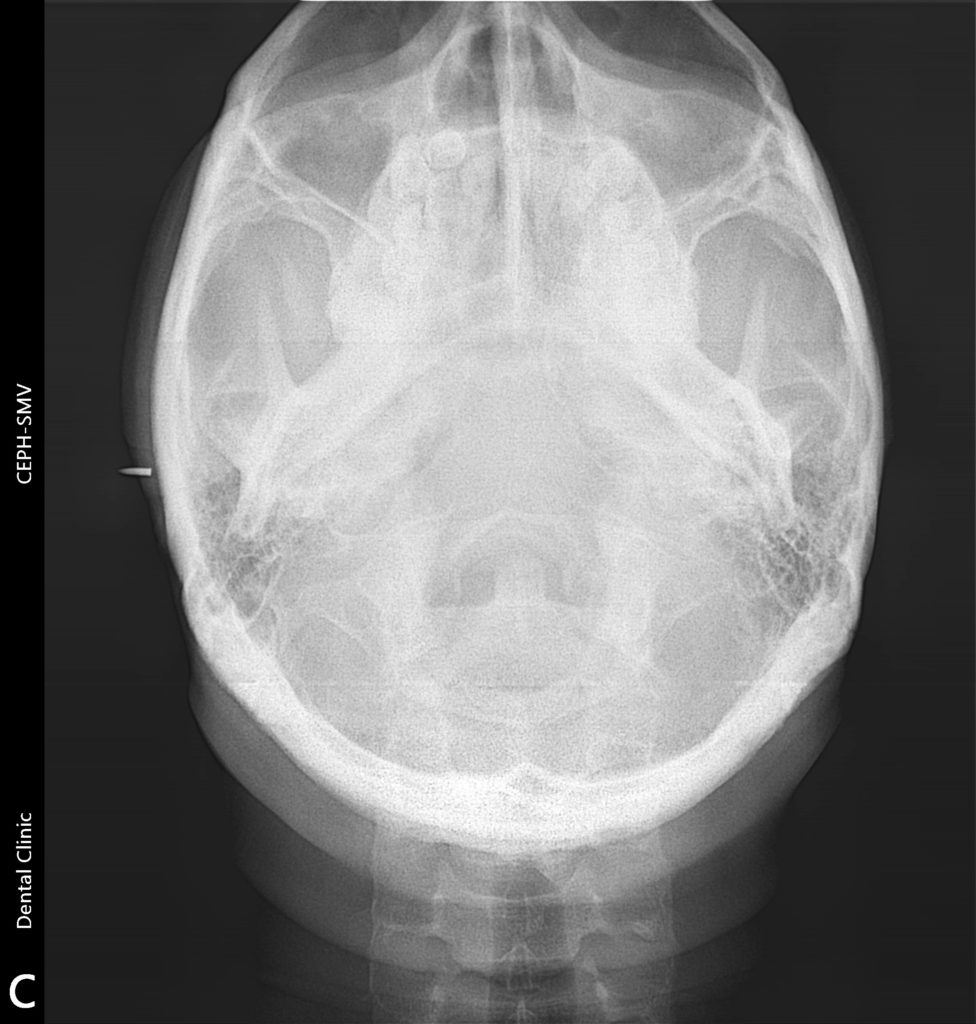

CBCT

Cone beam computed tomography (CBCT) is a special type of x-ray equipment used to produce three dimensional (3-D) images of your teeth, soft tissues, nerve pathways and bone. It provides superior quality and detailed images used for treatment planning and to evaluate dental implants, diseases of the jaw, dentition, bony structures of the face, nasal cavity and sinuses.